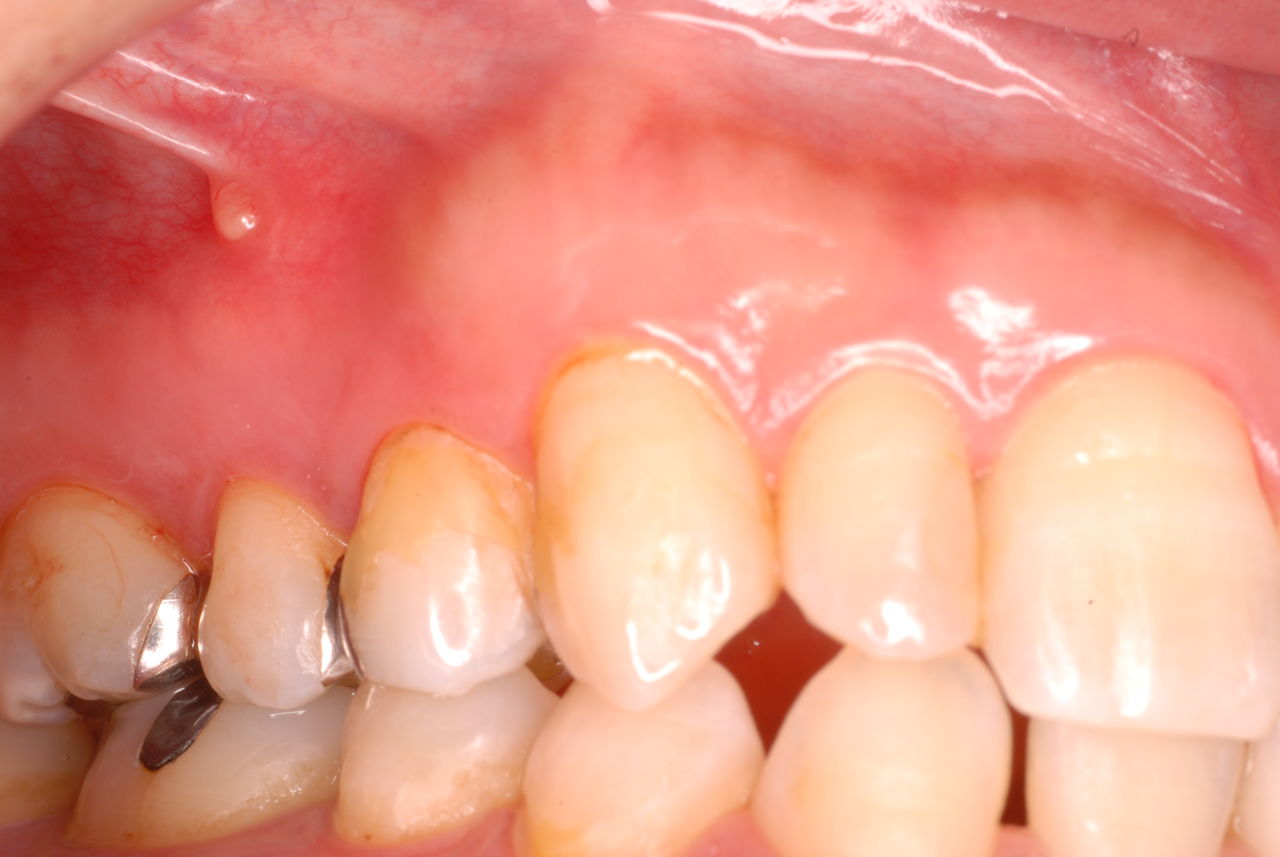

最近も5年ぶりに来た方がやはり同じような感じでした。

前回の来院時には痛みを止める為に歯に穴をあけ膿を吐き出させるような事をやっただけで来なくなった人です。

歯科医も患者も勉強する必要があるのかもしれません。

ため息が出ました。